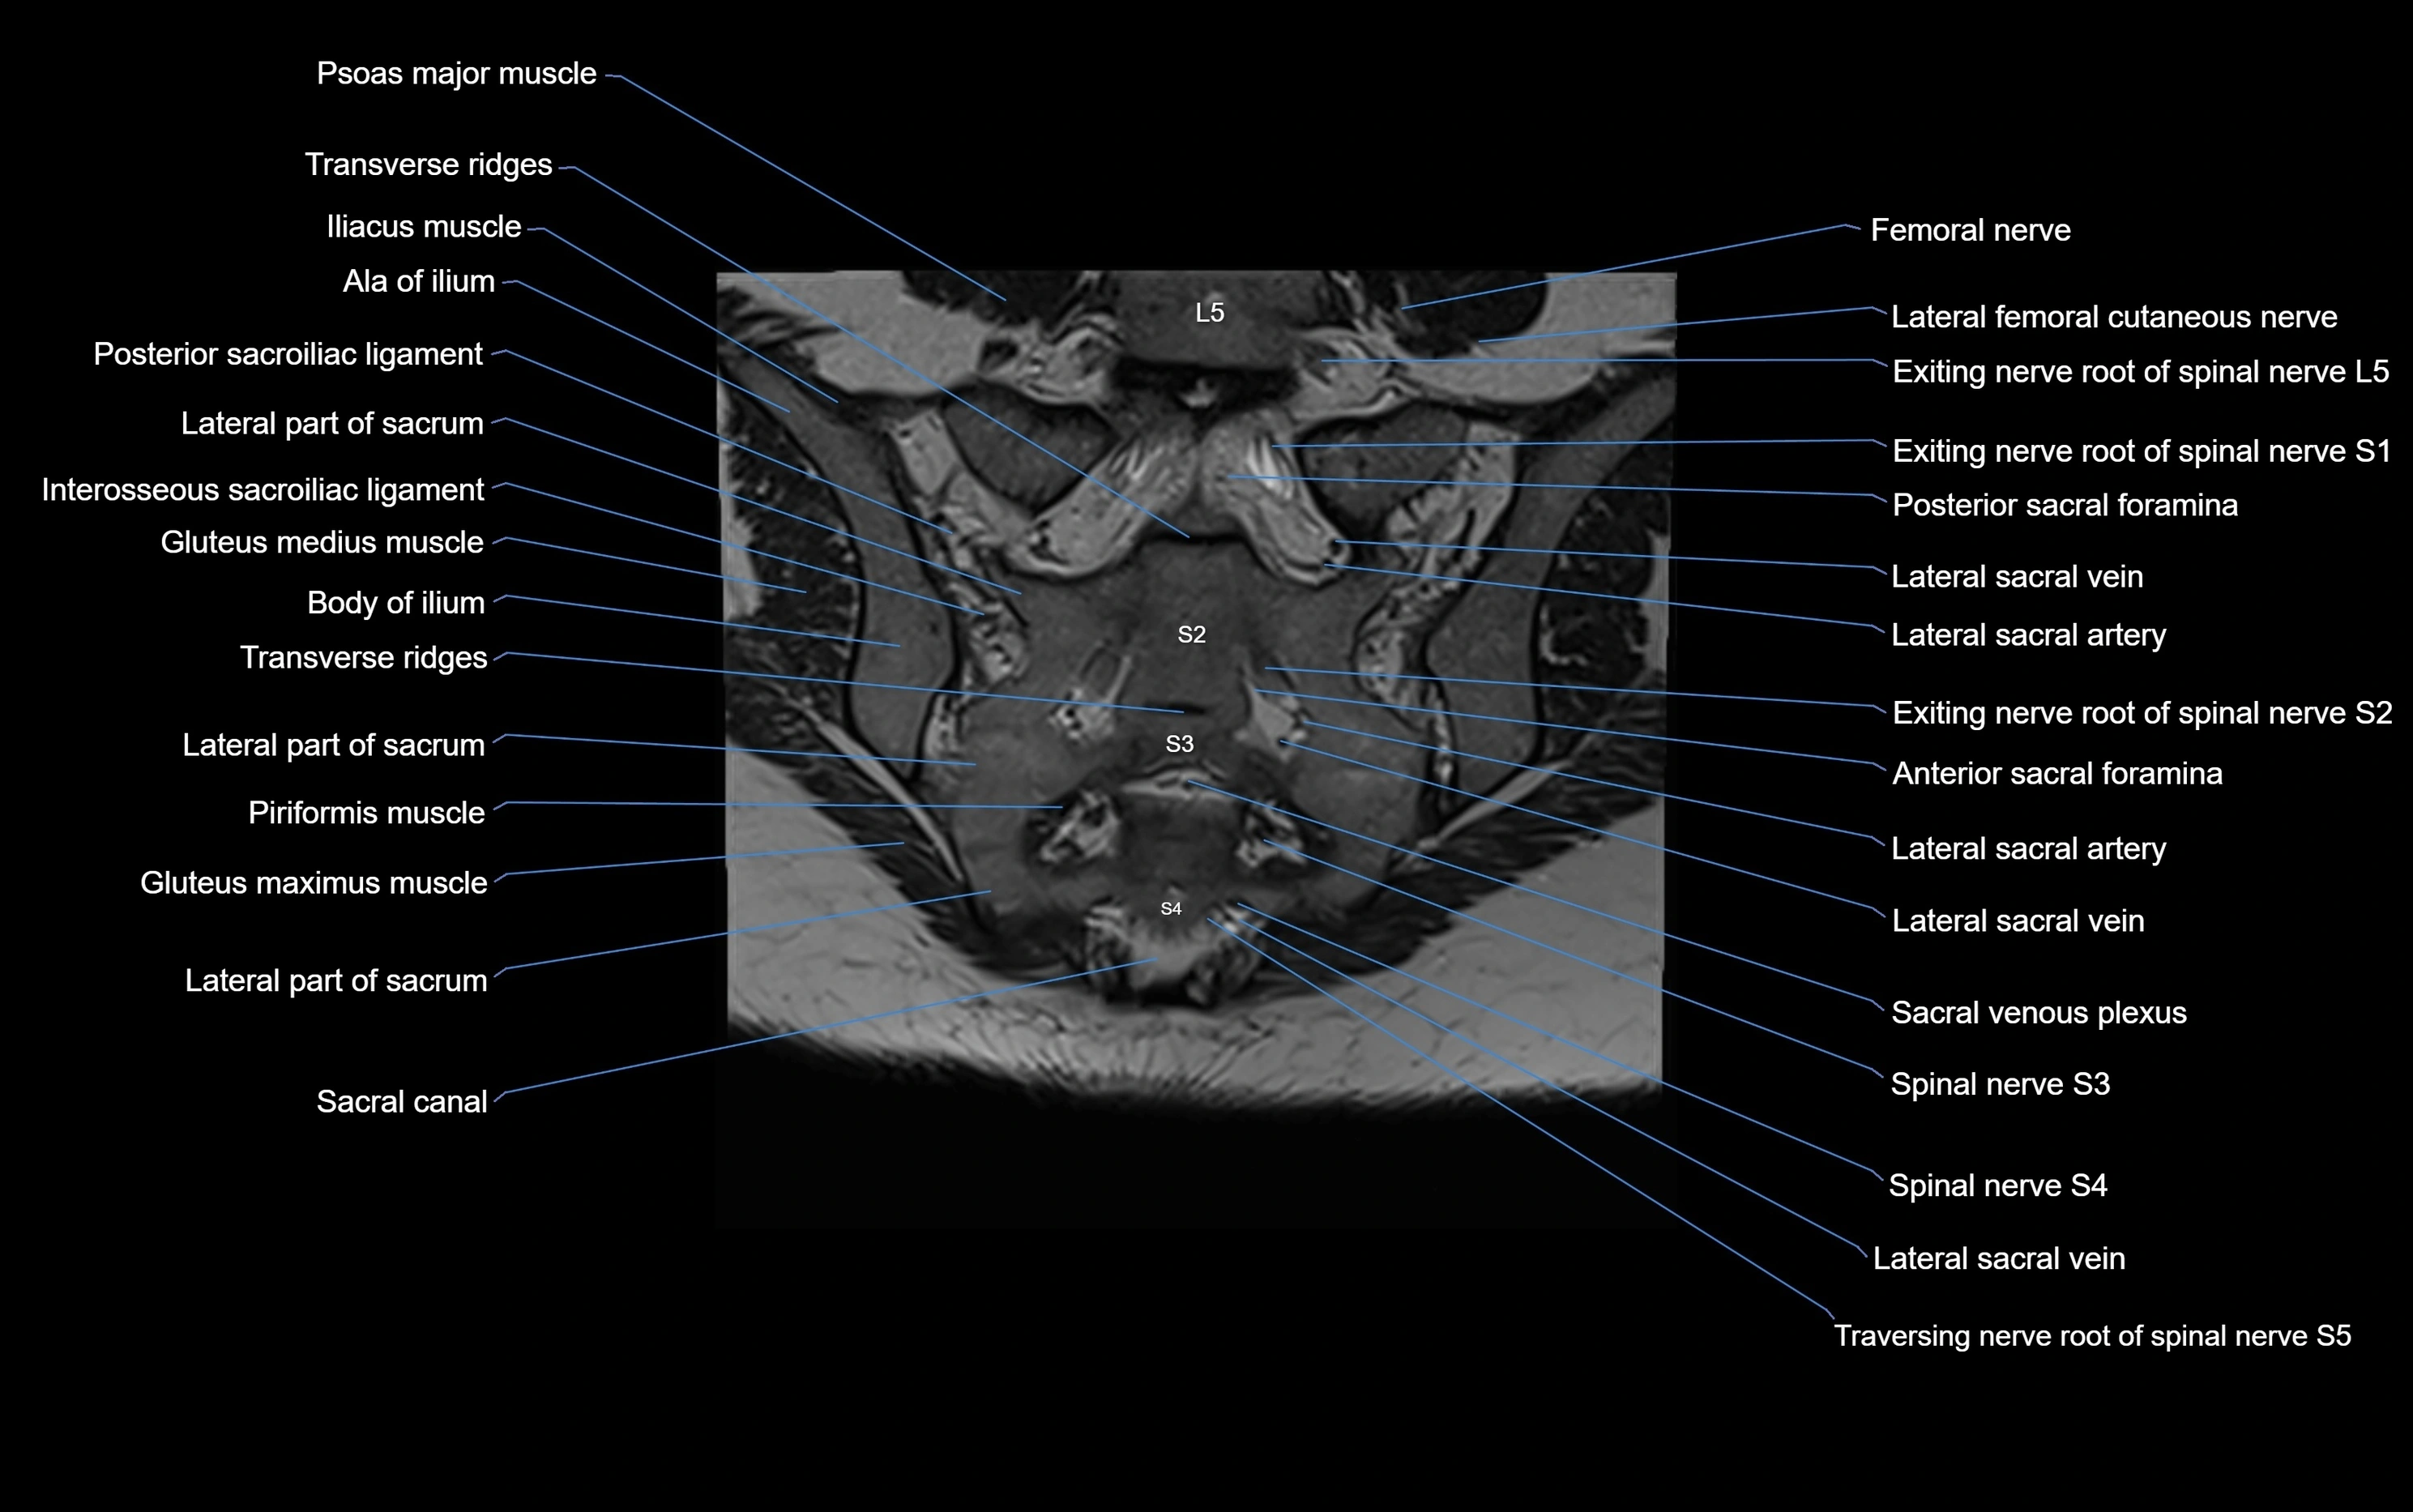

MRI image

image